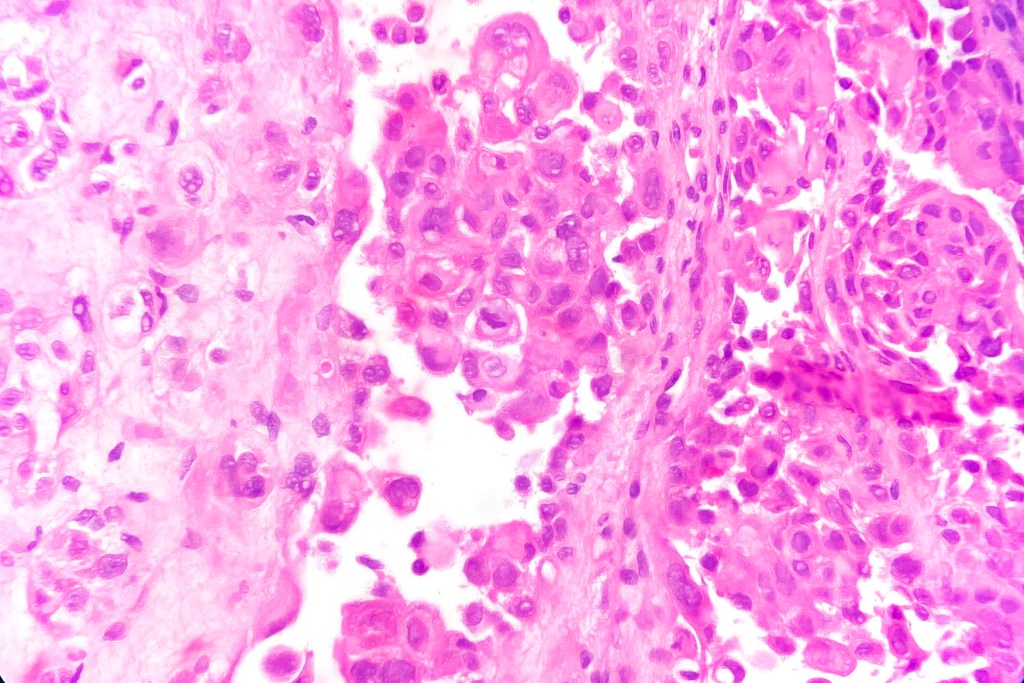

•Acantholysis gives rise to a pseudoglandular appearance

•Often well differentiated

•Variable pleomorphism & mitotic activity

•Exceptional associated signet-ring cell change (signet ring cell squamous carcinoma)